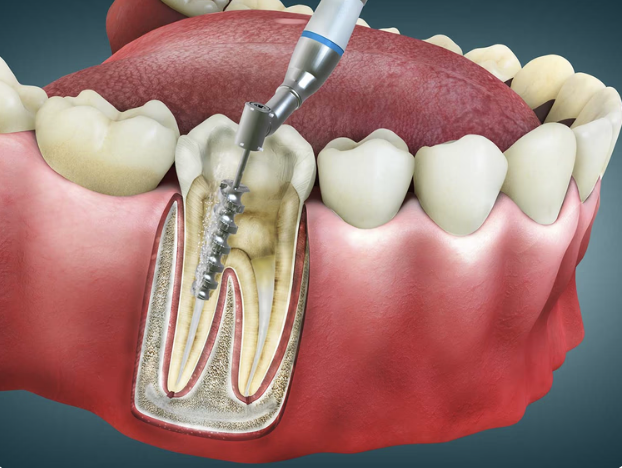

Endodontics - Root Canal Treatment

In the old days if you had a toothache you simply had the tooth pulled out. Nowadays people have become highly aware that extracting a tooth is not only going to be more costly in the long run but can cause detrimental instability of your occlusion resulting in tooth fractures, tooth tipping, gum disease and Tempro Mandibular Joint problems.

The alternative to extracting the tooth is Root Canal Treatment. A procedure which gets rid of the pain and allows you to keep your tooth.

Your tooth aches because the nerves and blood vessels in the centre of the tooth are deteriorating and forming an abscess or dying due to decay or trauma. If it’s a tooth that can be saved, we will suggest Root Canal Treatment.